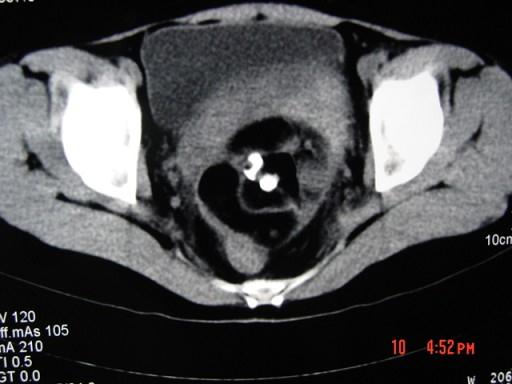

52岁女性患者,因下腹部胀痛就诊,B超提示:盆腔占位,行CT扫描,如图所示盆腔内见囊实性肿块,其内CT值不均,从-120至300hu不等,最可能的诊断为 ...

问题 52岁女性患者,因下腹部胀痛就诊,B超提示:盆腔占位,行CT扫描,如图所示盆腔内见囊实性肿块,其内CT值不均,从-120至300hu不等,最可能的诊断为 ( )

选项 A、卵巢囊肿 B、卵巢粘液瘤 C、盆腔结核 D、子宫肌瘤 E、盆腔畸胎瘤

答案 E